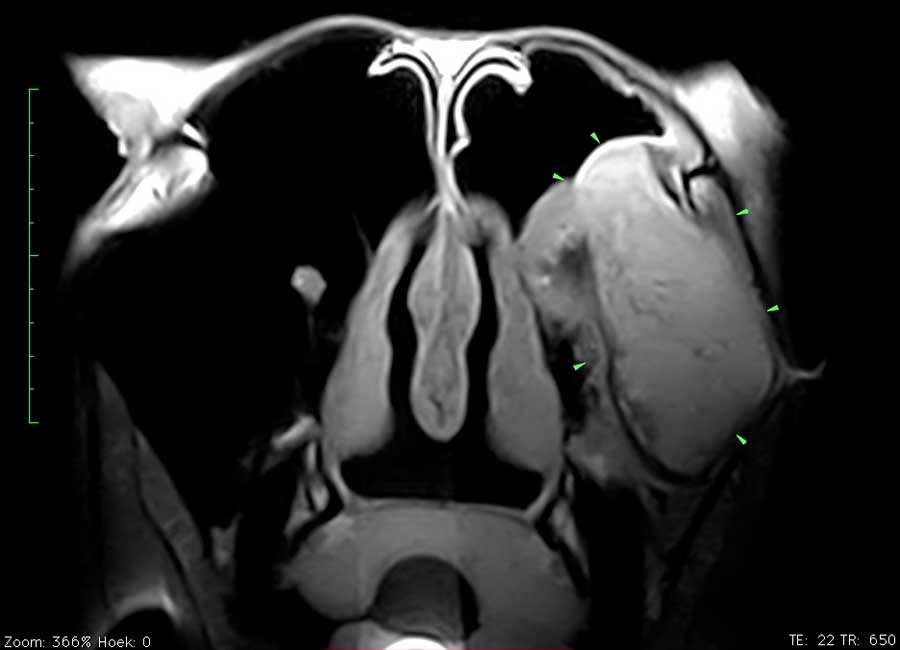

Dit paard had sinds enkele weken een unilaterale bloederige neusvloei. Op endoscopisch onderzoek was slechts een minimale afwijking ter hoogte van het linker ethmoid te zien. Radiografisch onderzoek toonde echter een grote massa in de sinus. Er werd beslist een pre-operatieve MRI uit te voeren om de operatie te plannen en ook de prognose beter te kunnen inschatten. Het ethmoid hematoom (PEH) bleek een groot deel van de linker sinus ingenomen te hebben.